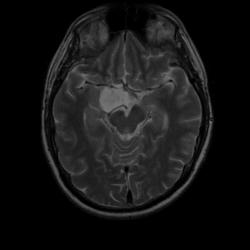

Женщина 47 лет, в течении долгого времени страдала от головных болей. В последние несколько месяцев - прогрессирующая потеря зрения (на оба глаза).

ИП FLAIR Axial

Presented images are corresponded for cerebral (right temporal-occipital region) neoplasia; high grade glioma is most suggested.

Глиальная опухоль.